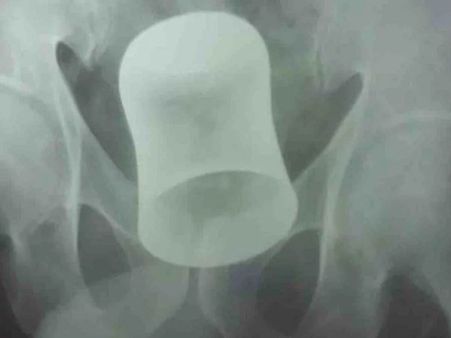

કાનપુરમાં બુધવારે એક ચોંકવી દેનારો કિસ્સો સામે આવ્યો છે. અહીં રામા હોસ્પિટલમાં હાજર ડૉક્ટરો 26 જૂને ચોંકી ગયા જ્યારે તેમને ખબર પડી કે દર્દીના પેટમાં સ્ટીલનો ગ્લાસ છે. એક્સ રે રિપોર્ટમાં પેટમાં ગ્લાસ હોવાનું માલુમ પડ્યા બાદ ડોક્ટરોએ બુધવારે ઓપરેશન કર્યુ. ડૉક્ટરએ પેટ ચીરીને ગ્લાસ બહાર કાઢ્યો. આ ઓપરેશન બે કલાક સુધી ચાલ્યુ. ઓપરેશન કરનાર ડૉક્ટરોએ આને રેરેસ્ટ ઓફ રેર કેસ ગણાવ્યો.

દર્દી પેટમાં પીડાની ફરિયાદ લઈને આવ્યો હતો. અલ્ટ્રાસાઉન્ડ કરાવતા પેટમાં ગ્લાસ ફસાયો હોવાનું જાણવા મળ્યુ. ગ્લાસ આંતરડામાં ફસાઈ ગયો હતો. 27 જૂને એનેસ્થેટિસ્ટ ડૉ. રાજીવ કુમાર, ડૉ. અમિત, ડૉ. રોહિત, ડૉ.આશિષ સાથે મળીને રામદીનનું ઓપરેશન કર્યુ. પેટમાં ચીરો મૂકીને ગ્લાસ કાઢવામાં આવ્યો.

ઓપરેશન કરનાર રામા હોસ્પિટલ એન્ડ રિસર્ચ સેન્ટરના સીનિયર સર્જન ડૉ. દિનેશ કુમારે આને રેર ઓફ ધ રેરેસ્ટ કેસ ગણાવ્યો છે અને આ ઓપરેશનને મોટી સફળતા ગણાવી છે. ઓપરેશન લગભગ 2 કલાક સુધી ચાલ્યુ હતુ જેમાં દર્દીના પેટને ચીરીને ગ્લાસ કાઢવામાં આવ્યો હતો. તેમણે જણાવ્યુ કે તે આને મેડીકલ મેગેઝીનમાં પ્રકાશિત કરવા માટે મોકલશે.